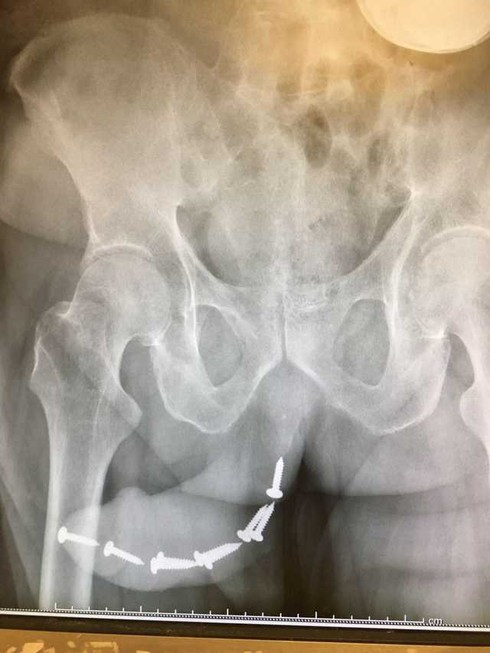

BS Dung cho biết, bệnh nhân ở Hà Nội đến phòng khám trong tình trạng tiểu buốt. Khám không có nấm nhưng chảy máu ở đầu dương vật, bác sĩ chỉ định bệnh nhân đi chụp phim thì phát hiện hàng loạt chiếc đinh cấy bên trong.

| Quý ông cấy gần chục cái đinh vít vào dương vật. |

Bệnh nhân được sang chuyên khoa Tiết niệu, gây mê và phẫu thuật gắp dị vật ra ngoài.